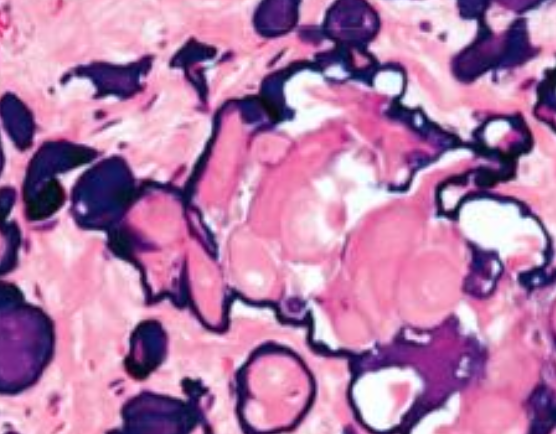

玻片特徵

- Developmental cyst

- epithelial lining 與結締組織交界處平整

- 非發炎型(noninflamed)

- 結締組織鬆散

- 糖胺聚醣基質(glycosaminoglycan ground substance)。

- 發炎型(inflamed)

- 網嵴(rete ridges)

- cholesterol clefts

- 齒源 → Rushton bodies